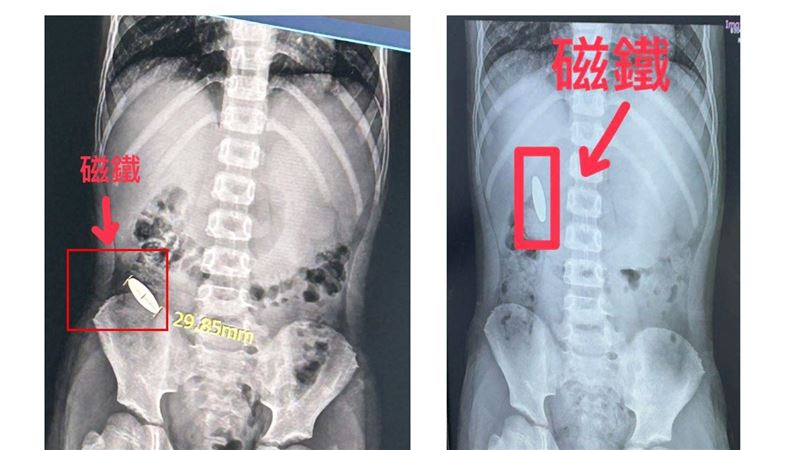

聯合報

「我的磁鐵會不會一直卡在肚子裡?」台南傳出補習班霸凌事件,方姓家長近期向市議員林燕祝陳情,因6歲兒子27日在校外補習班疑...

台南市安南區一間補習班上個月27日爆發一起嚴重霸凌案,一名還在就讀小一的男童居然被小五的學長逼吞10元硬幣大小的磁鐵,但補習班卻在事發後未進行相關通報,受害男童的家長要求看監視器氣憤時卻聲稱「硬碟壞掉」,直到男童2天後向學校老師告知時,才將這起霸凌案曝光,受害家長2日在國民黨市議員林燕祝陪同下召開記者會,傷心的表示磁鐵目前還在小朋友的腸道中,而且兒子的身心狀況不佳,半夜還會驚醒問爸爸「磁鐵會不會一